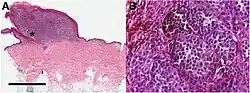

Histopathologic types

Melanoma is a type of neuroectodermal neoplasm.[85] There are four main types of melanoma:[86]

SN Type Features Incidence[86][notes 1] Photograph Micrograph

1. Superficial spreading melanoma Melanoma cells with nest formation along the dermo-epidermal junction. 70%

2. Nodular melanoma Grows relatively more in depth than in width. 15% - 20%

3. Lentigo maligna melanoma Linear spread of atypical epidermal melanocytes as well as invasion into the dermis.[87] 5% - 10%

4. Acral lentiginous melanoma Continuous proliferation of atypical melanocytes at the dermoepidermal junction.[88] 7% - 10%